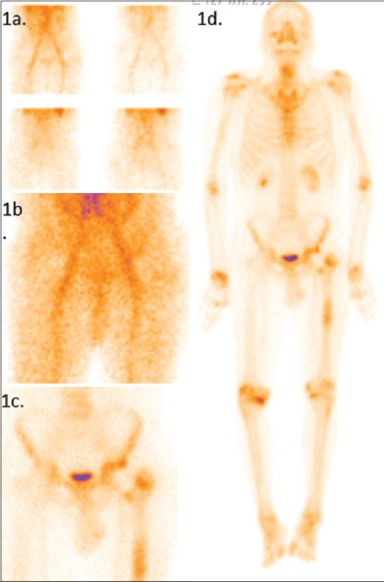

Uomo di 40 anni, sottoposto a sostituzione dell’anca con protesi 2 anni prima, si è presentato con dolore sordo all’anca sinistra e a metà coscia.

La radiografia dell’anca è risultata nella norma, mentre la VES era lievemente elevata. A causa del dolore persistente, il paziente è stato sottoposto a scintigrafia ossea trifasica con 99mTc-MDP.

Le immagini di flusso (1a) hanno mostrato una vascolarizzazione normale in entrambe le articolazioni coxo-femorali. L’immagine di blood-pool dell’anca (1b) ha evidenziato un minimo aumento dell’accumulo del tracciante nell’articolazione coxo-femorale sinistra, prevalentemente lungo la superficie acetabolare. L’immagine statica tardiva (1c) e l’immagine whole-body (1d) hanno mostrato un lieve aumento della captazione nella superficie acetabolare sinistra e una captazione focale nella regione intertrocanterica all’interfaccia osso-protesi. Diagnosi: mobilizzazione asettica.